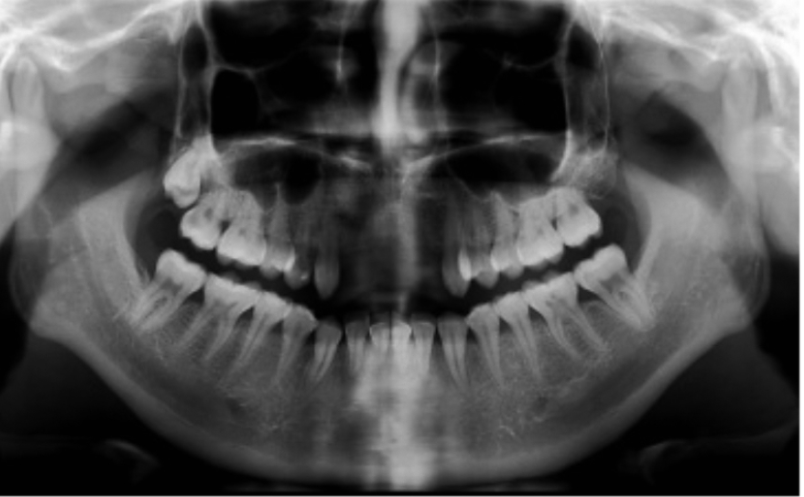

图5 术前全景片

图6 术后全景片

(二)CBCT帮助准确判断

由于全景X线机设计的原因,前牙区必然会受到颈椎、咽腔重叠的影响,常常显示的影像不是很清楚,而且前牙区的水平失真率变化较大,有时候可以看见种植体形状发生改变。必要时可常规拍摄CBCT,以了解骨质高度、宽度以及骨质的密度的状况,有利于种植方案的确定以及植入角度的判断。